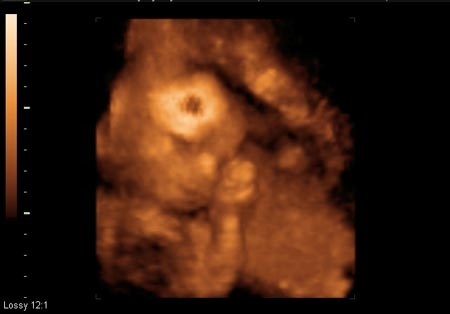

MiniMimi egész jól viselte a kukucskálást, amit kértem tőle, azt maximálisan próbálta teljesíteni, igazából nem lehetne panaszra okom, mutogatta, amit kellett, elég egyértelműen. Az egyetlen gond, amire nem is számítottam, hogy az arcát viszont takargatta a kezével, vagy belefúrta a fejét a méhlepénybe, így a pofijáról egy képet leszámítva nem sikerült jó képet csinálni. Talán még az is közrejátszott, hogy a mellső falon tapadt meg a méhlepény, így ez is nehezítette a nézelődést. Ettől függetlenül nagyon jó élmény volt, jó volt látni, ahogy mozog, forgolódik, dörzsölgeti a kis szemét.

A súlya már több mint fél kg és a hossza 27 cm, 4 cm-es hatalmas talpacskákkal. Érdekes volt látni, hogy a 2D-s képeken már látszottak a kis fogkezdemények az ínyében.

A nemét egyértelműen sikerült megmutatnia, nagyon ügyesen felhúzva tartotta a lábait, amíg alulról a doki bácsi megszemlélte. Az orvos kicsit érdekesen kezdte el felvezetni a nemét: közölte, hogy itt kellene lennie a herezacskónak, de olyan hangsúllyal mondta, mintha valami rendellenesség lenne. Aztán hozzátette, hogy itt pedig a hímvesszőnek, tehát, ha nincs ott egyik sem, akkor milyen nemű lesz - nézett ránk kérdőn… Ez itt egy kislány.